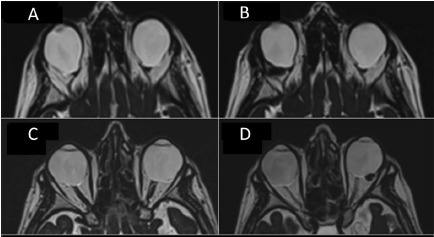

7.png

图 8 A 为眼眶 T2 TSE 轴 MRI,双眼球后部黄斑及乳突葡萄肿畸形;B 为同一只眼扣带术后 1 月 MRI,右眼球后壁变平;C 为另一患者眼眶 T2 TSE 轴 MRI,双眼球后部黄斑及乳突葡萄肿畸形,从底部观察到左眼有一黄斑脱离;D 同图 C 为同一只眼,扣带术后 1 月 MRI,左眼眼球后壁扣带处轻微突起。